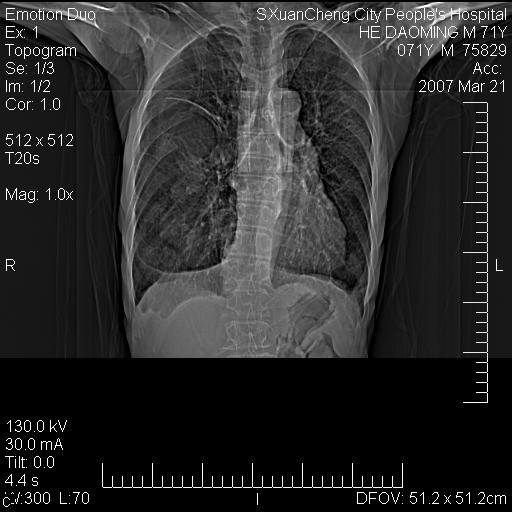

标题: CT7269:[原创] 咳嗽,咳痰,大家讨论右肺病变的部位 [打印本页]

标题: CT7269:[原创] 咳嗽,咳痰,大家讨论右肺病变的部位

右侧相当于叶间软组织样密度ct值约50hu,请大家讨论是什么性者病变